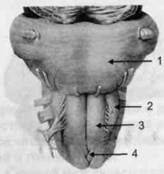

Задний мозг состоит из продолговатого мозга, мозжечка и моста (варолиева) (рис. 8 и 9). Продолговатый мозг анатомически является продолжением спинного, хотя по внутренней структуре и соотношению серого и белого

веществ заметно от него отличается. Продолговатый мозг включает в себя ряд ядер, обслуживающих управление дыханием, сердечным ритмом, сосудистым тонусом и рядом других функций, в том числе артикуляторных (поддерживающих согласованную работу органов речи для обеспечения членораздельного произношения).

В продолговатом мозгу находится ряд рефлекторных центров, связанных с процессами пищеварения. Это группа центров моторных рефлексов (жева-

Рис. 8. Средне-нижние отделы головного мозга: J — зрительная хиазма; 2 — латеральное коленчатое тело; 3 — медиальное коленчатое тело; 4 — подушка таламуса (фрагмент); 5 — бугры четверохолмия; 6— мозжечок; 7— спинной мозг; 8 — продолговатый мозг; 9— варолиев мост; 10— ножки мозга; // — гипофиз

Рис. 10. Передняя поверхность заднего мозга: / — варолиев мост; 2 — оливы; 3— пирамиды; 4— перекрестье пирамид

ния, глотания, движении желудка и части кишечника), а также секреторных (слюноотделение, выделение пищеварительных соков желудка, поджелудочной железы и др.). Кроме того, здесь находятся центры некоторых защитных рефлексов: чихания, кашля, мигания, слезоотделения, рвоты.

Продолговатый мозг играет важную роль в осуществлении двигательных актов и в регуляции тонуса скелетных мышц — участвует в осуществлении рефлексов поддержания и восстановления позы тела, так называемых установочных рефлексов. Как филогенетически древнейший отдел головного мозга, он имеет важное значение в осуществлении функций сна.

На передней поверхности продолговатого мозга имеются два вертикальных валика, получившие название пирамид. По бокам от них расположена другая пара валиков, обозначаемых как оливы (рис. 10).

Варолиев мост — это крупное поперечно-волокнистое образование, охватывающее передне-верхнюю часть продолговатого мозга. В функцию моста входит проведение координирующих импульсов от одного полушария мозжечка к другому для обеспечения согласованных движений мышц на обеих сторонах тела и связь коры больших полушарий с самим мозжечком. В варо-